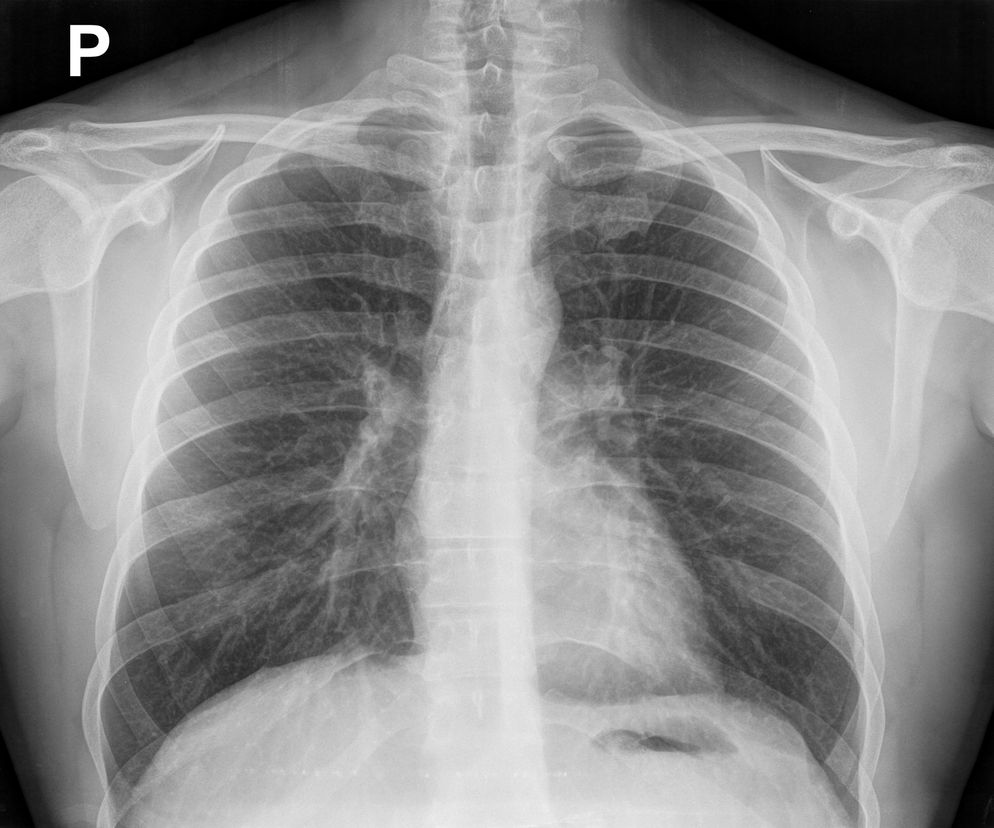

Rentgen (RTG, prześwietlenie) klatki piersiowej to badanie radiologiczne. Badanie rtg służy do oglądania płuc i dróg oddechowych. Sprawdź, jak wygląda przygotowanie do badania RTG klatki piersiowej i na czym ono polega.

rentgen klatki piersiowej

Autor: Getty Images

Rentgen (RTG) klatki piersiowej oznacza prześwietlenie klatki piersiowej promieniami rentgenowskimi.